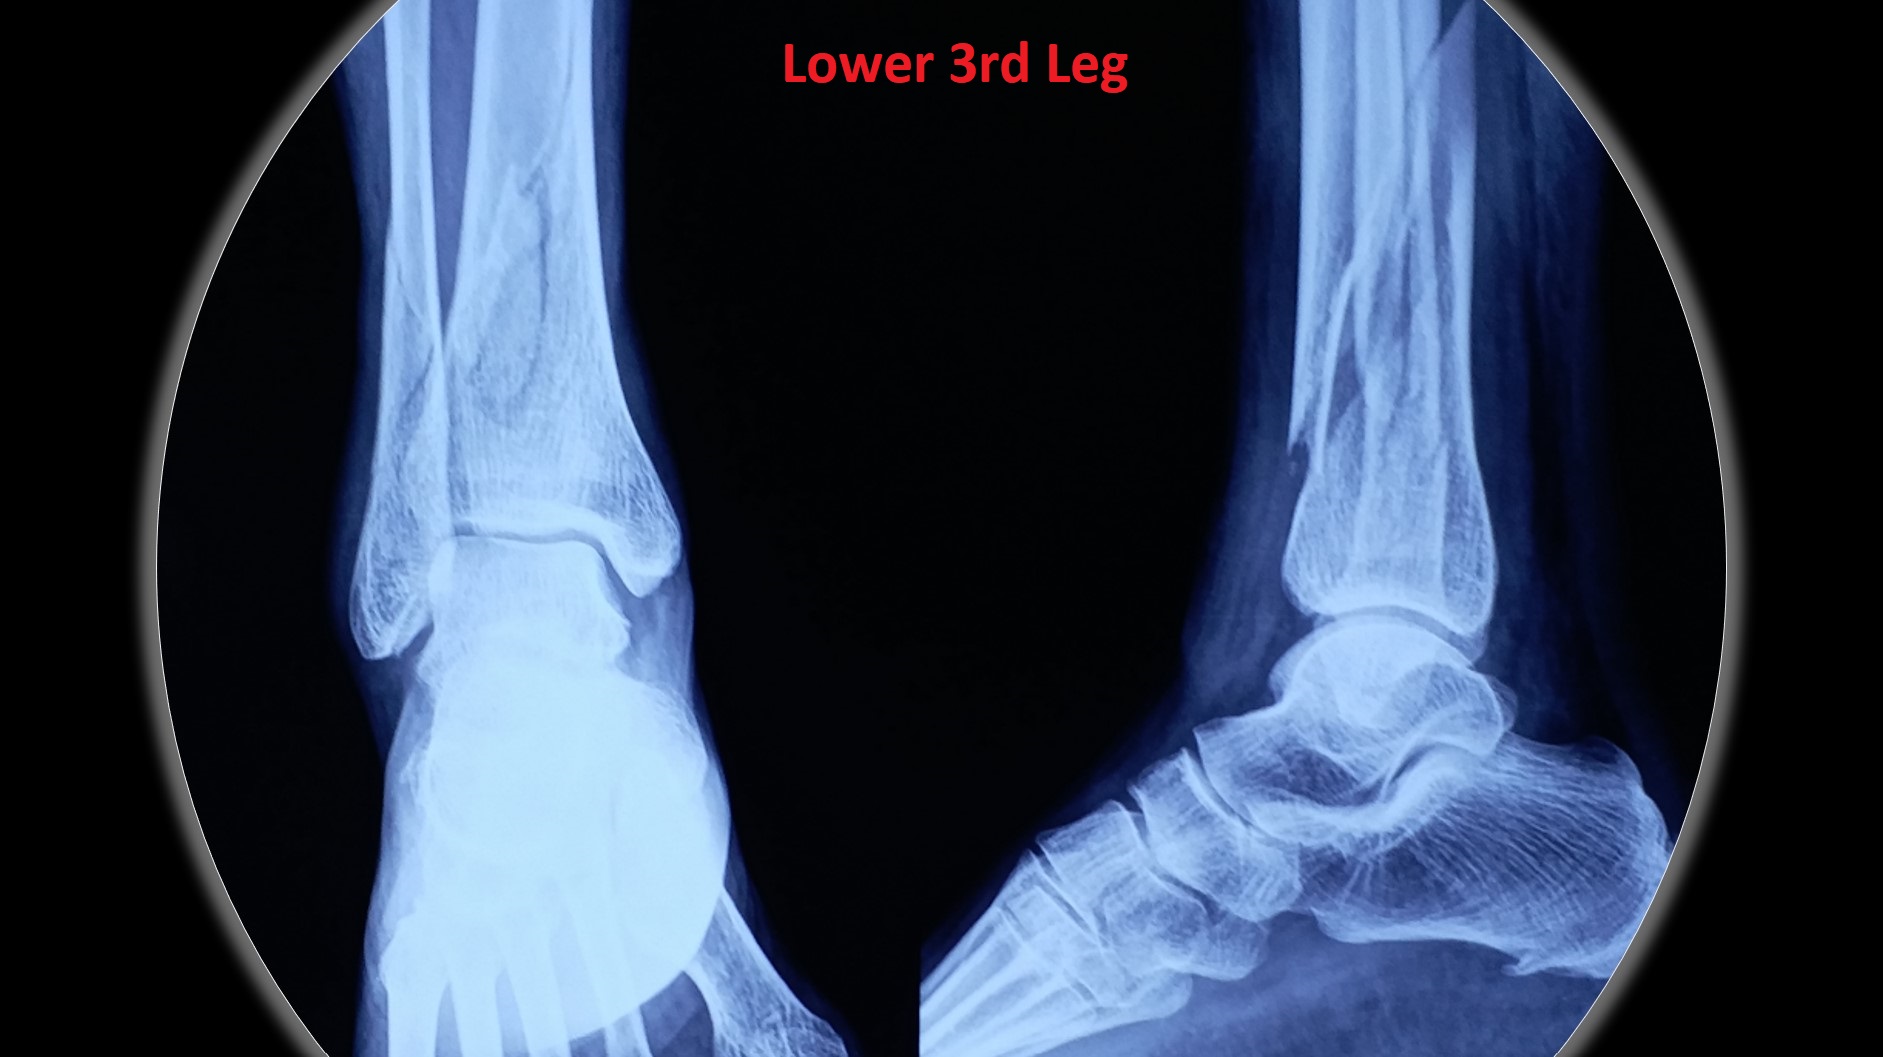

• It can be applied to any intraarticular fractures, distal end radius, elbow, ankle and foot.

• Most of the metaphyseal fractures of both upper and lower limbs can be successfully treated by CRPP.